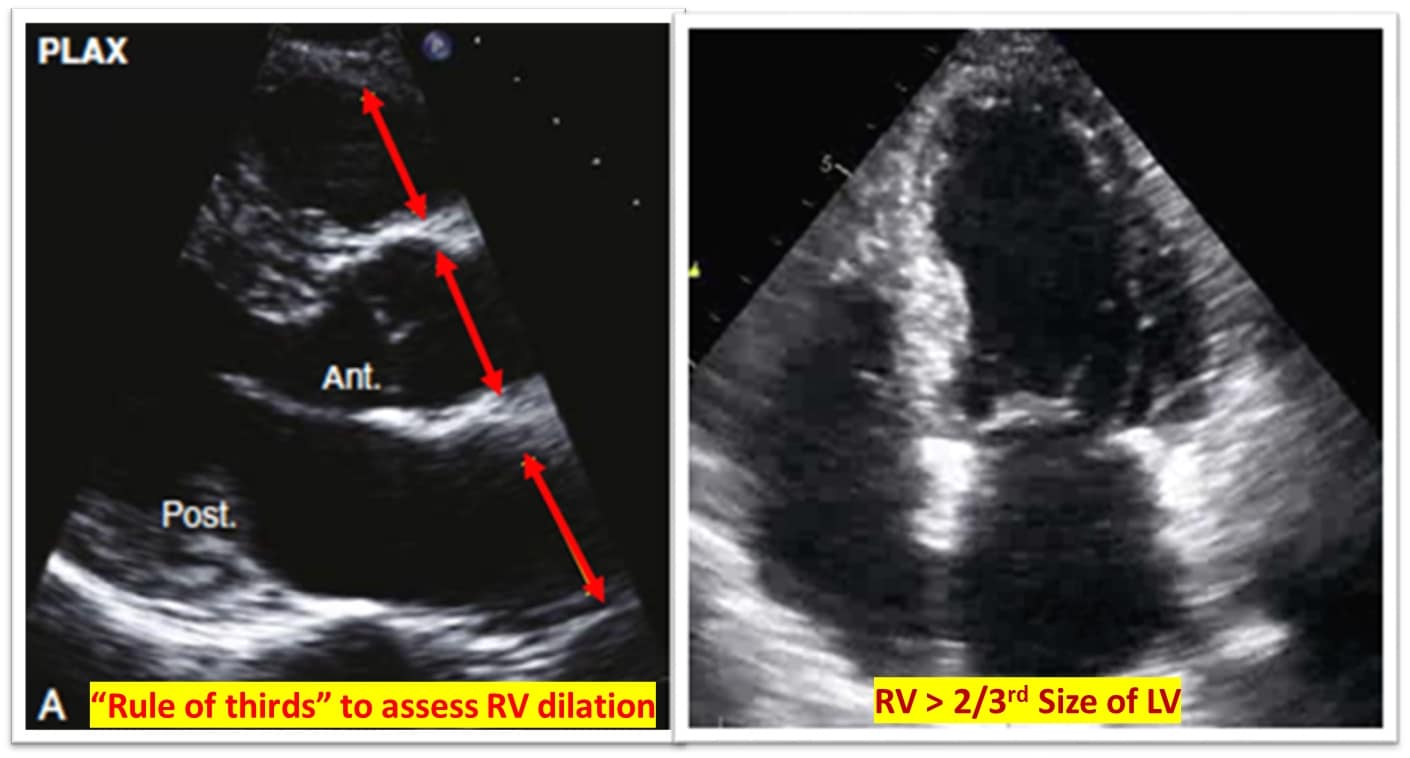

RV assessment can be qualitative or quantitative with attention to RV size, systolic function, pulmonary hemodynamics, or a combination thereof. The visual assessment of RV size and function begins in PLAX, using the “rule of thirds” to uncover the presence of RV dilation (Figure 2). In A4C or the RV-focused view, qualitatively, RV size >2/3 of LV size is considered dilated.7,8 Quantitatively, RV enlargement is present when the RV basal diameter is > 41 mm at the point of the tricuspid valve (TV) insertion to the RV free wall (RVFW) or RV mid-cavity dimension is >35 mm at the level of the open anterior TV leaflet on RVFW.10,11 A RV end-diastolic area to left ventricular end-diastolic area (RVEDA: LVEDA) >0.6 defines moderate RV dilation, while area of (RVEDA: LVEDA) ≥1 suggests severe RV dilation or acute cor-pulmonale, especially when septal dyskinesia is present.10, 12 McConnell’s sign is another qualitative sign of acute cor-pulmonale characterized by dyskinesia of the RVFW with relative sparring of the RV apex (Video 4). It is important to note that the reliability of measurements to assess RV size and function increases with further training and practice.13 (Figure 3)

Figure 2: Qualitative RV dimensions.

RV = right ventricle, LV = left ventricle